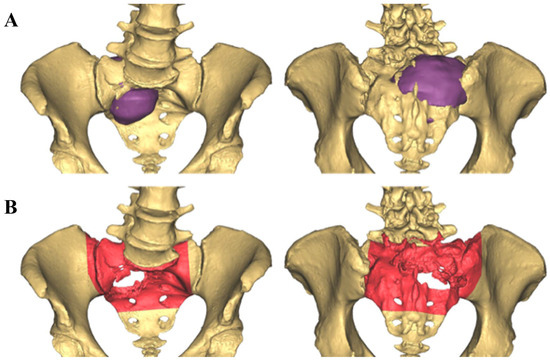

2.1. CAD Development

2.2. Intraoperative CAD Utilization

| Procedures Performed | Stage 1: L5-S1 anterior discectomy, anterior sacral osteotomy, fibula flap harvest Stage 2: sacrectomy, L3-pelvis PSIF, L5-pelvis ASF with vascularized fibula flap, VRAM flap | Stage 1: Rt T12-pelvis PSIF, L3-5 laminectomy, fibula flap harvest; Stage 2: L4, L5 vertebrectomy, sacrectomy, Lt type I internal hemipelvectomy, Lt L3-pelvis PSIF Stage 3: L3-pelvis ASF with vascularized fibula flap | Lt type I-II internal hemipelvectomy, custom endoprosthetic pelvic and hip joint reconstruction | Lt Type I internal hemipelvectomy, vascularized fibula autograft reconstruction | Stage 1: L3-S3 laminectomy, L5 vertebrectomy, L3-pelvis PSIF; Stage 2: Lt type I internal hemipelvectomy, Lt partial sacrectomy, L5-pelvis ASF with vascularized fibula autograft | L5-S1 laminectomy, partial sacrectomy, Lt ilium osteotomy, pedicled Rt gluteus maximus flap |